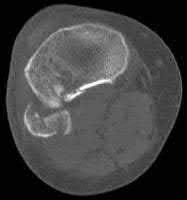

A 38-year-old male suffers the injury shown in Figure A. During operative fixation, free osteoarticular fragments are encountered and reconstruction of these pieces is attempted. Postoperatively, which of the following will have the most beneficial effect on the healing potential of the surviving chondrocytes within these reconstructed articular segments?

Figure A demonstrates a comminuted tibial plateau fracture with significant intra-articular involvement. Basic science evidence has demonstrated that post-operative gentle compressive loading may have a positive impact on articular cartilage healing; however, excessive shear loading may be detrimental.

Irrgang et al provide guidelines for rehabilitation following surgical management of articular cartilage lesions of the knee. They state that after articular cartilage repair, exercises to enhance muscle function must be done in a manner which minimizes shear loading of the joint surfaces in the area of the lesion. The authors also discuss the benefits of gentle compressive loading and motion of the joint, and its positive effects on chondrocyte nutrition.

Furthermore, they recommend a period of protected weight bearing as often being necessary, and that this should be followed by progressive loading of the joint.

Illustration A is a diagram showing the different layers of joint cartilage.